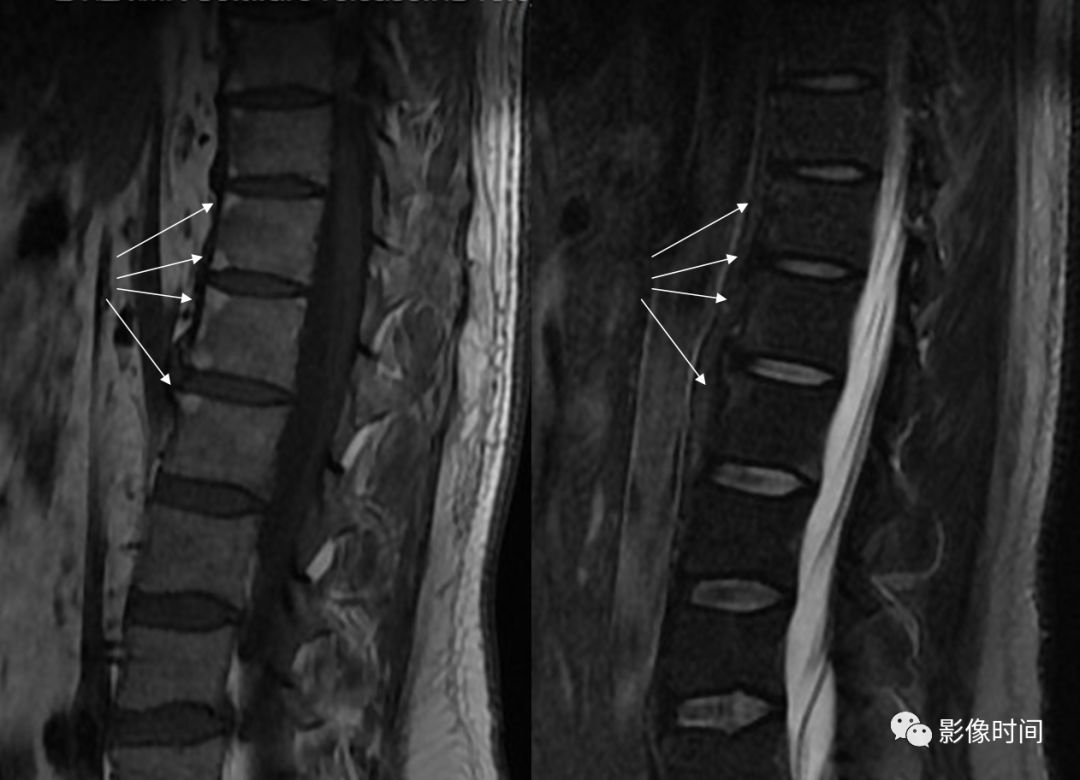

16跳跃征

在脊椎的 MR 各序列中,脊柱的椎体和/或附件多节段受累时,呈现病变脊椎之间有正常脊椎(箭示)的不连续改变,称为跳跃征。常见于脊椎转移瘤。

典型病例

67 岁男性,前列腺癌脊椎转移。磁共振 T1WI 及 T2WI 图像示多椎体多发病灶(箭示),大小不等,分布呈现跳跃征。